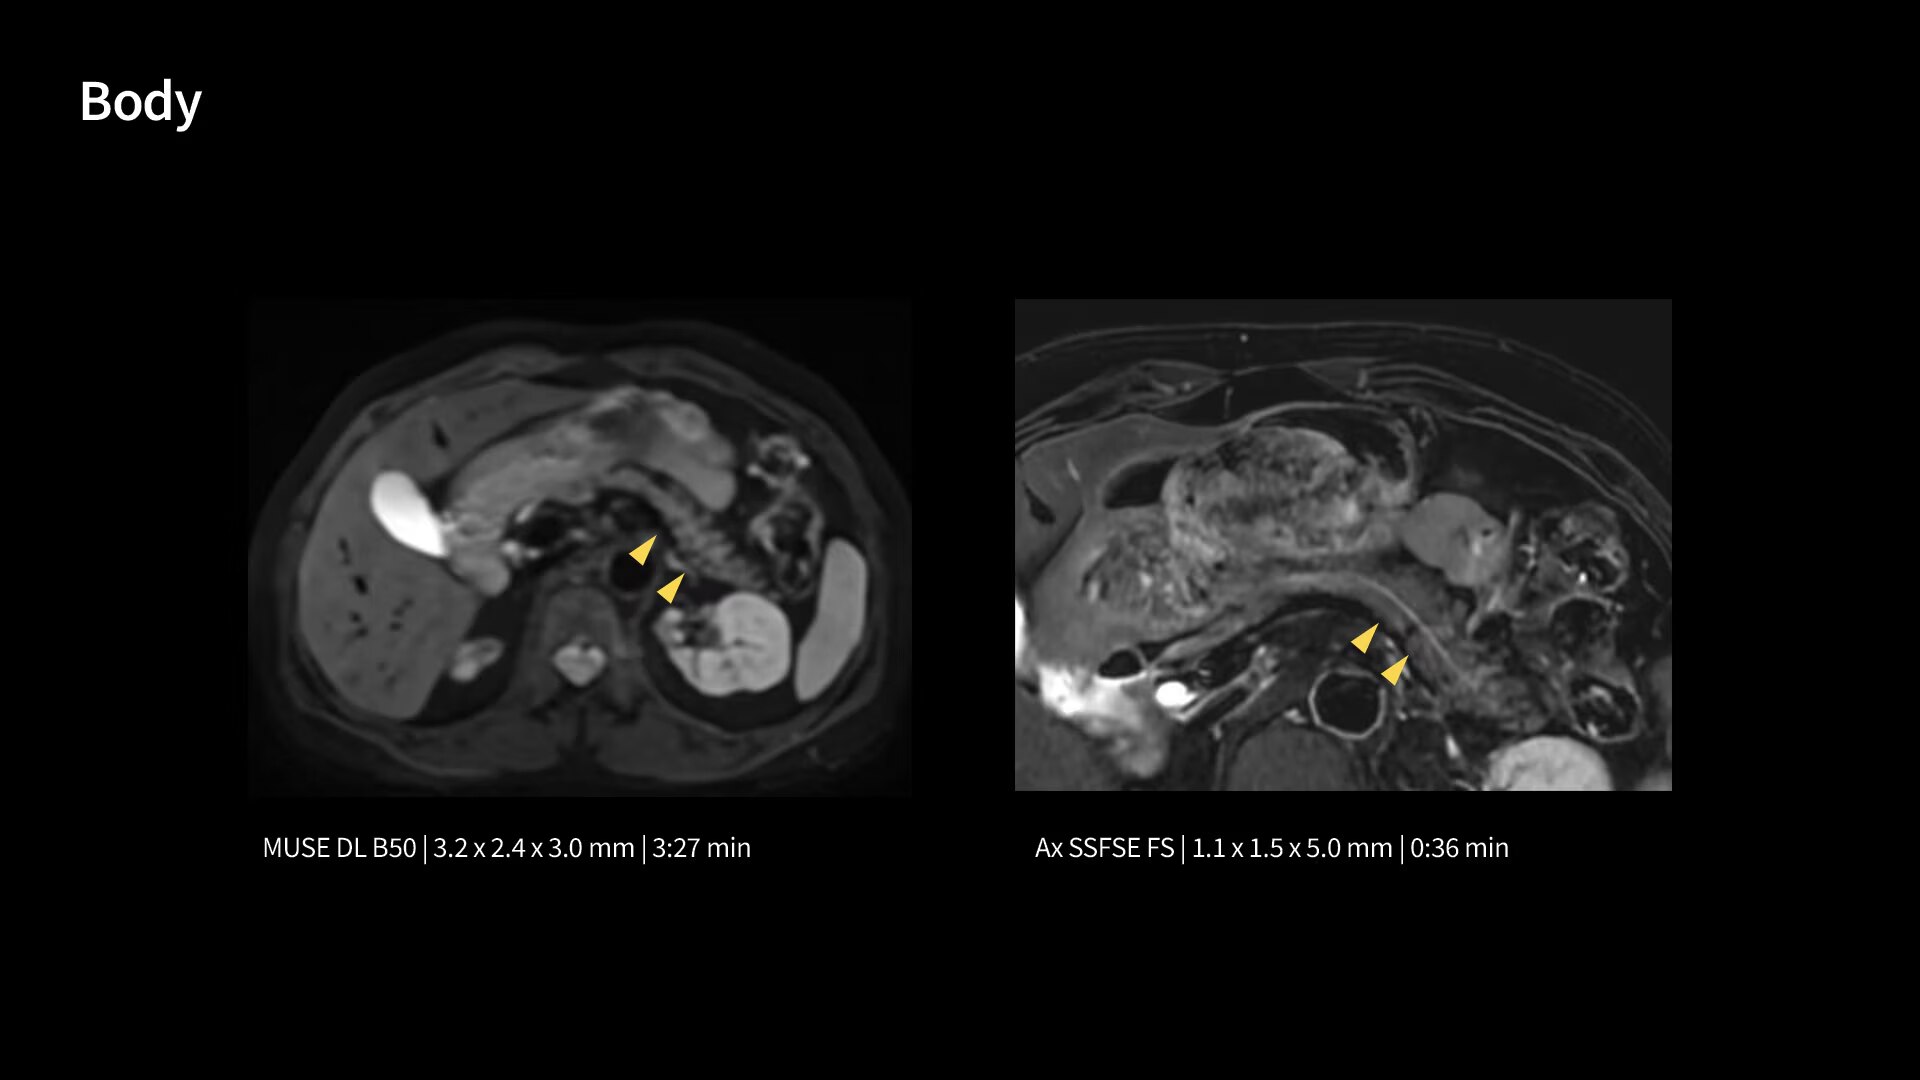

In oncological assessments, diffusion imaging is a critical clinical indicator. SIGNA Sprint offers clearer diffusion, reduced distortion and improved SNR.¹